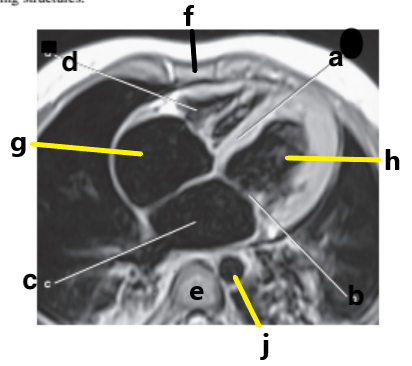

What is letter a ?

Right ventricle

What is letter h ?

Left ventricle

What is letter d ?

What is letter g ?

Right atrium